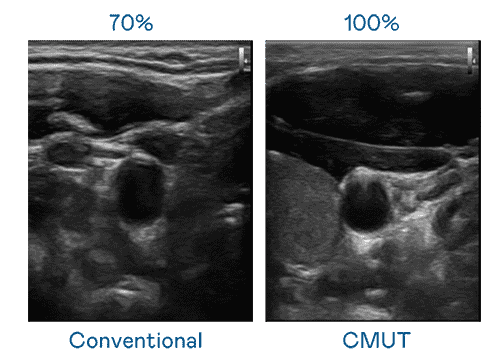

CMUT 技术是一种用电容式微机电元件来产生超音波讯号的技术。。与传统 PZT 压电式技术相比,,,CMUT 频宽增加 30%,,更宽频的超音波讯号让影像解析度大幅提升,,,,是实现高影像品质医疗超音波扫描、、促进精准医疗发展的关键技术。。

大频宽带来超清晰影像

超音波影像的解析度高低,,首先取决于探头能发出的讯号频宽。。。。龙门国际 CMUT 可提供高清晰的超音波讯号,,,提供高频宽、、、高灵敏度、、影像纹理细节更高的超音波影像,,,协助医护人员缩短影像判读时间及利用精准的医疗影像进行诊断。。